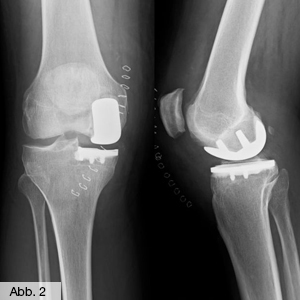

Das künstliche Kniegelenk

Wenn der Gelenkknorpel vollständig zerstört ist (es reibt Knochen auf Knochen), bleibt in der Regel das Einsetzen einer Gelenkprothese als einzige Methode übrig. Mit Hilfe modernster Technik wird je nach Bedarf ein Teil oder das gesamte Gelenk durch ein Implantat ersetzt. Hierfür bietet die Orthopädie Erwitte als Endoprothetikzentrum der Maximalversorgung ein breites Spektrum an Verfahren (s. EndoProthetikZentrum).

Unser Konzept beim Kniegelenkersatz ist es, eine bestmögliche Gelenkfunktion mit geringstmöglicher Opferung von Knochen und Gewebe zu ermöglichen. Daher verwenden wir als Standardprothese den so genannten Oberflächenersatz, bei dem nur so viel Knochen entfernt wird, wie es die Einbautiefe der Prothese erfordert. Die Bänder (Seitenbänder und hinteres Kreuzband) bleiben erhalten und gewähren die Stabilität und Kinematik des Gelenks.

Bild Orthopädie Knie Schlittenprothese